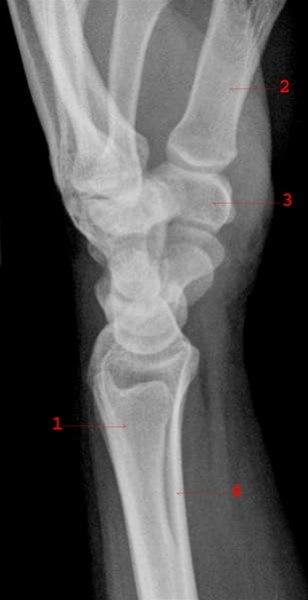

Normalt sidebilde av håndledd med håndrotsknokler

1. Ulna

2. 1. metakarp

3. Os trapezium

4. Radius